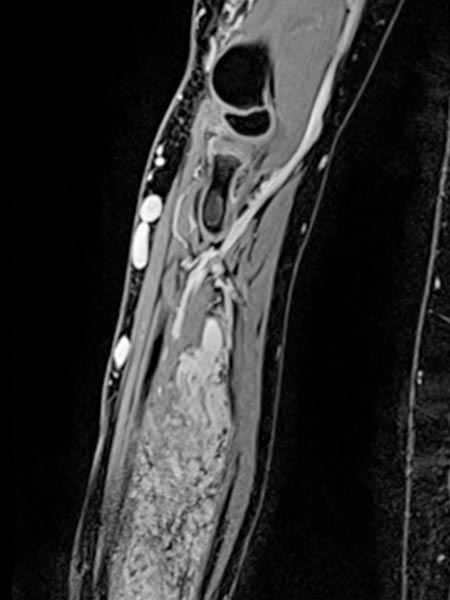

The coronal, T2-weighted, fat-suppressed sequence of an MRI with imaging of the right upper and lower arm shows a much larger extension of the malformation than clinically suspected.

The extension is predominantly subfascial in the depth of the muscles of the upper and lower arm. The signaling is strongly hyperintense, thus certainly a slow-flow malformation (venous or lymphatic).

The venous malformation shows deep extension in the deep flexor tendons of the hand and forearm on T2-weighted, fat-suppressed MRI.

On the distal right forearm in the area of the main extension of the swelling, the bulk of the venous malformation is seen predominantly in the flexor muscles. Severely hyperintense MRI signal in T2w fat saturation. The entire flexor muscles are intermingled.